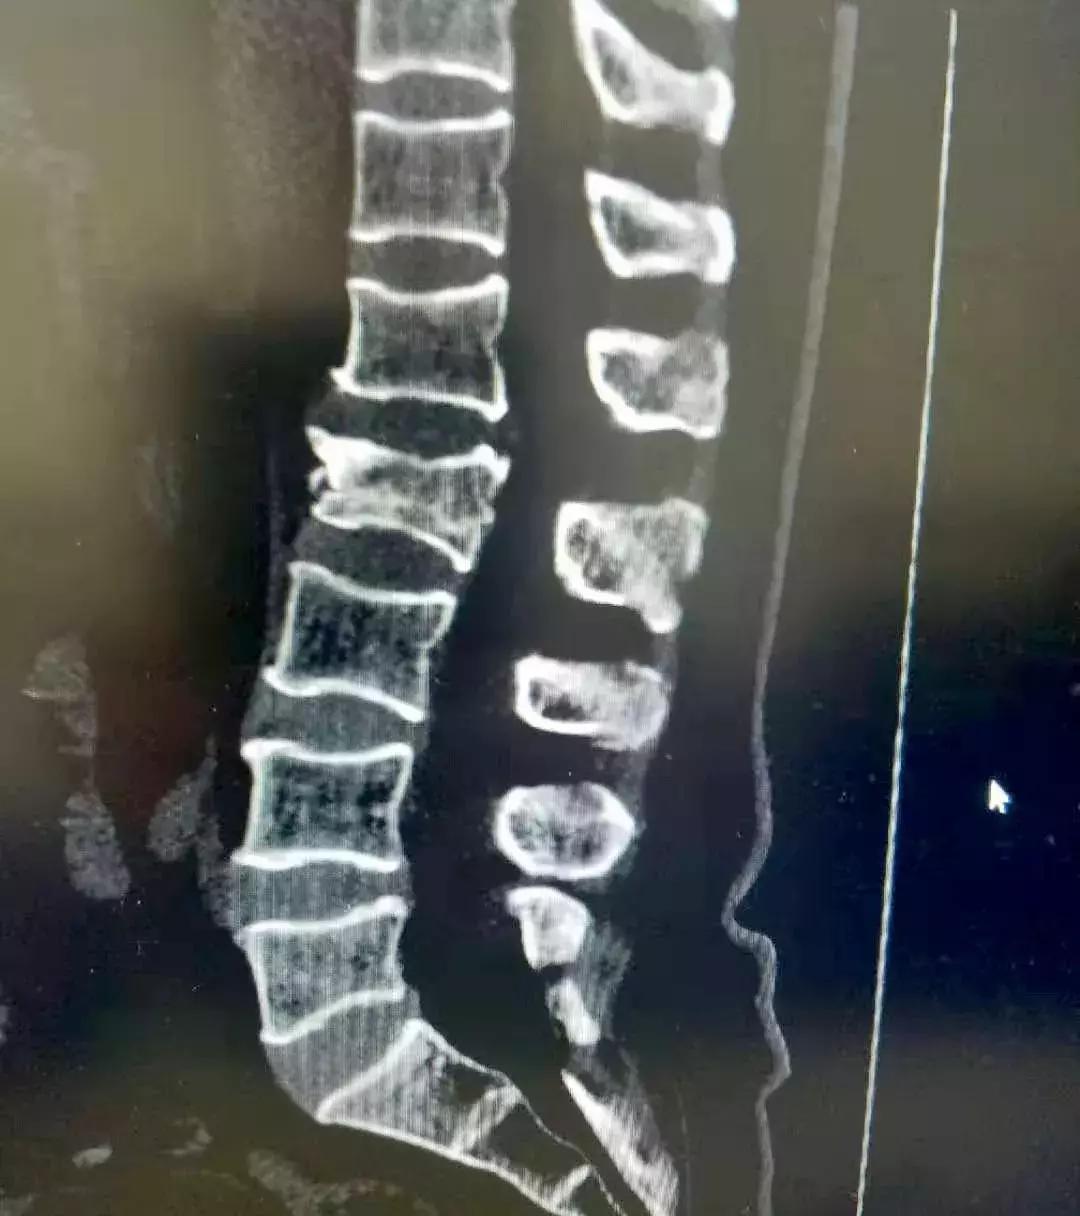

术前第二腰椎压缩性骨折,压缩1/2椎体